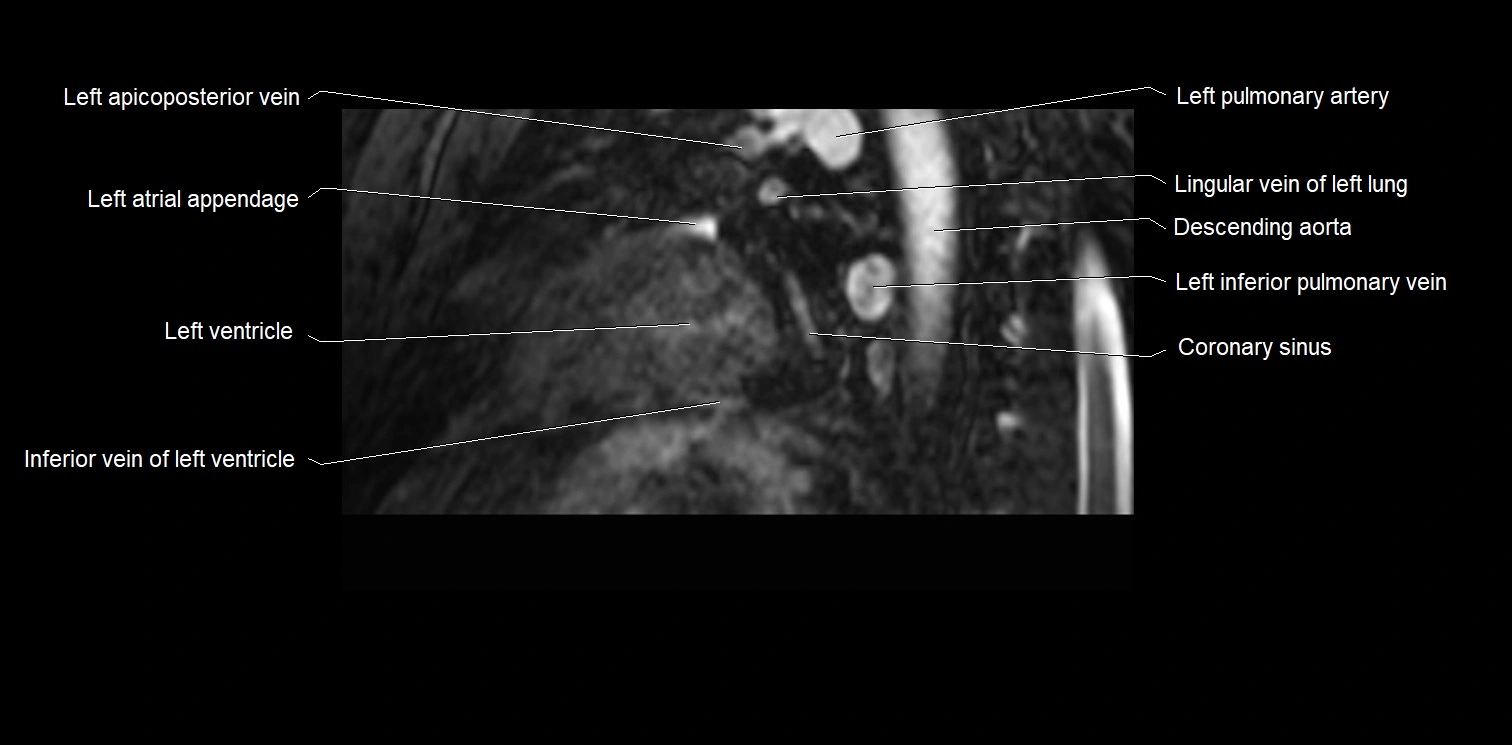

MRI image